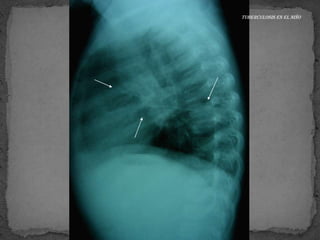

Transmisión por vía aérea por gotitas.

Siempre que estemos

ante un infiltrado alveolar

y adenopatía

hiliar/mediastino hay que

pensar TB

Complejo de Ranke o primario

 La proyección debe ser AP y lateral para identificar

adenopatías

 TB primaria se caracteriza por la presencia de

adenopatías hiliares o paratraqueales con infiltrados

alveolares